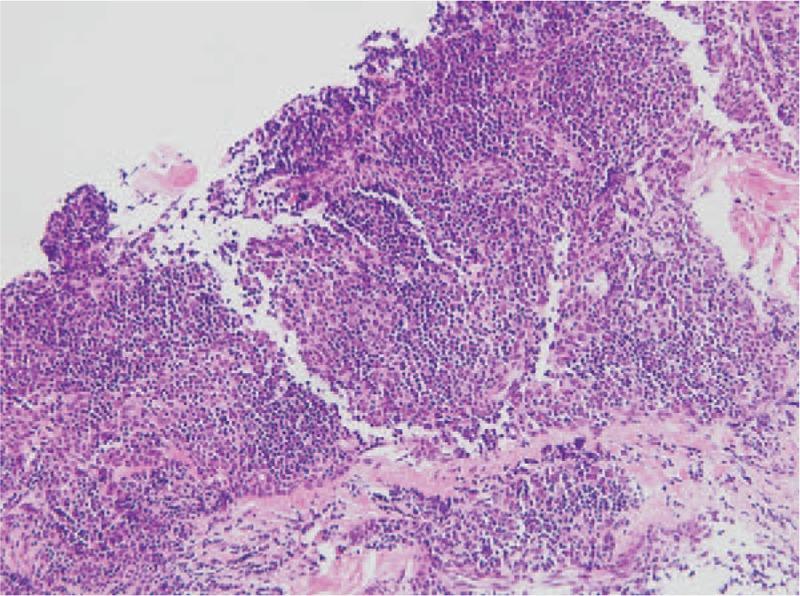

We report a 32-year-old female with nephrotic syndrome that was first diagnosed along with invasive thymoma and treated by means of cisplatin-based chemotherapy for the thymoma. The patient initially presented with dyspnea and generalized edema. Chest radiography and computed tomography scans revealed right pleural effusion and a mass in the right middle lung field, which were confirmed by a percutaneous lung biopsy as metastatic invasive thymoma. Severe hypoalbuminemia, heavy proteinuria, hyponatremia, and hypercholesterolemia were features of the nephrotic syndrome. A kidney needle biopsy suggested focal segmental glomerulosclerosis.

我们报告一名32岁女性,最初被诊断为肾病综合征合并侵袭性胸腺瘤,并接受了以顺铂为基础的胸腺瘤化疗。患者最初表现为呼吸困难和全身水肿。胸部X线和计算机断层扫描显示右侧胸腔积液和右中肺野肿块,经皮肺活检证实为转移性侵袭性胸腺瘤。肾病综合征的特征为严重低白蛋白血症、大量蛋白尿、低钠血症和高胆固醇血症。肾穿刺活检提示局灶节段性肾小球硬化。